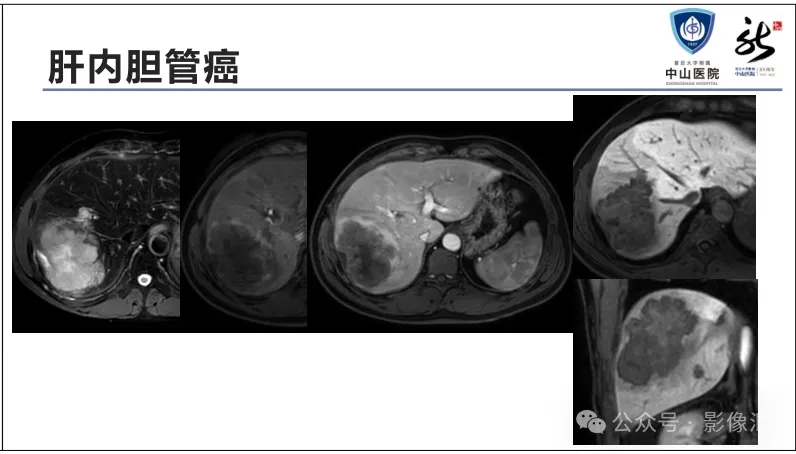

肝胆特异性对比剂增强肝胆图像判读方法与策略,课件来源于网络,作者复旦大学附属中山医院放射科饶圣祥教授。